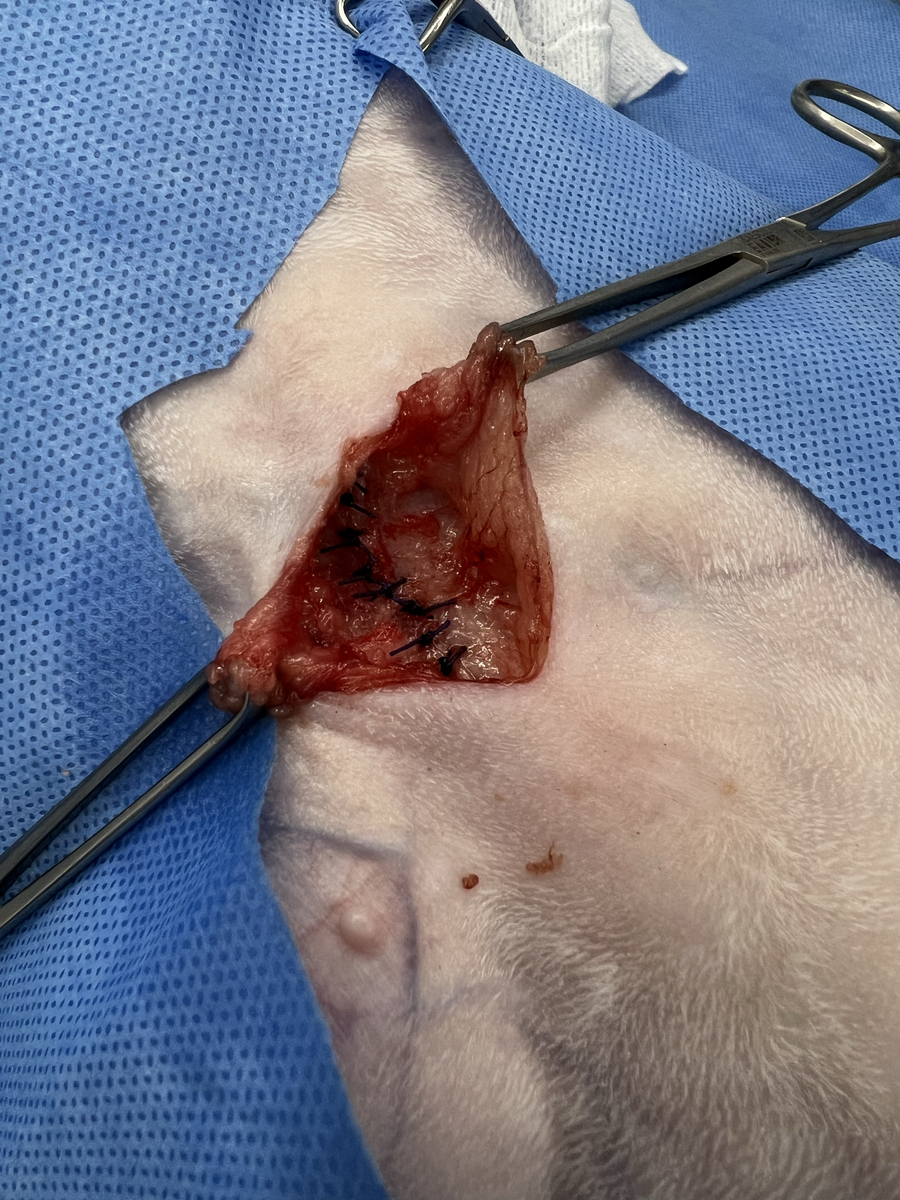

初診の時点では、食欲や元気はあり吐き気や排便障害などの消化器症状はなかったので保護者様と相談の上、手術は見合わせていたのですが、先日お腹の膨らみが徐々に大きくなってきたという事で、空いてしまっているお臍の所と腹壁の穴を閉じる手術を行いました。

開いてしまった所から飛び出ていた脂肪組織などを腹腔内に戻して、腹壁を縫合しました。